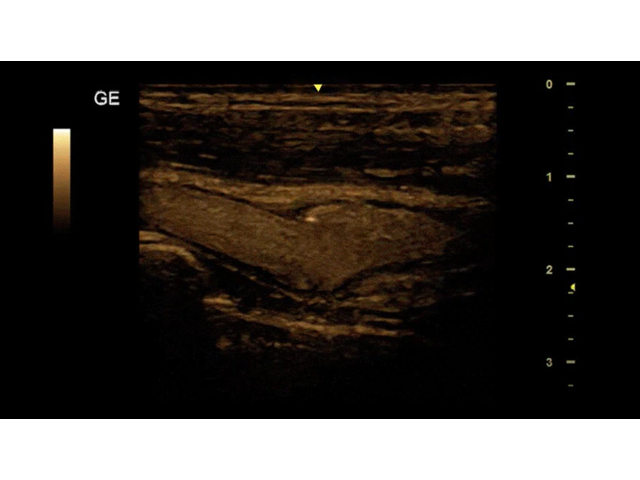

УЗИ-аппарат

GE Versana Essential

Ультразвуковой сканер GE Versana Essential отличается высокой точностью и мобильностью. Он широко используется при обследовании скелетно-мышечной системы и является незаменимым инструментом в урологии, гинекологии, педиатрии и общей радиологии.

Благодаря передовым технологиям и инновационным функциям, ультразвуковой сканер GE Versana Essential обеспечивает высокую четкость и детализацию получаемых изображений. Он позволяет врачам проводить диагностику и оценку состояния тканей и органов с высокой точностью, что способствует более точным и эффективным клиническим решениям.